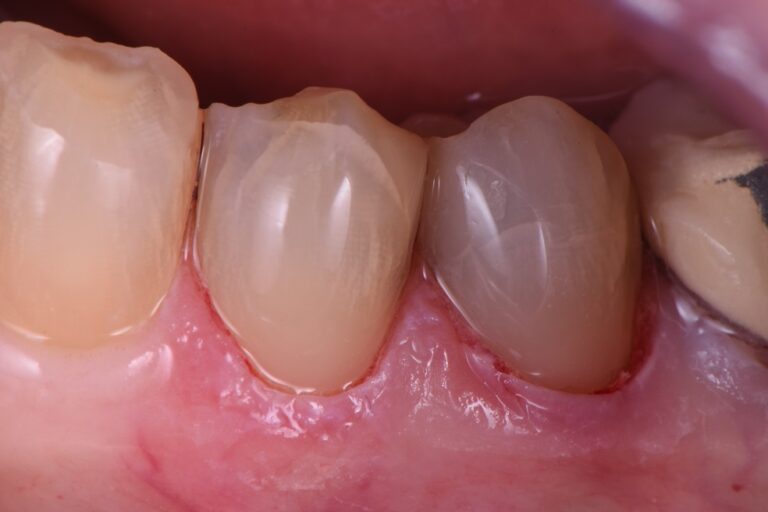

Sinais e sintomas da periodontite

A dor é geralmente ausente, a não ser que uma infecção aguda se desenvolva em uma ou mais bolsas periodontais, ou se houver periodontite associada ao HIV. A impactação alimentar nas bolsas pode causar dor durante as refeições. Placa bacteriana abundante, associada a hiperemia, edema e exsudato, é característica. As gengivas podem ser sensíveis e sangrar facilmente, e a respiração pode estar comprometida. À medida que os dentes amolecem, particularmente quando apenas um terço da raiz está no osso, a mastigação torna-se dolorosa.

Inspeção de dentes e gengiva, combinada à exploração das bolsas gengivais e aferição de suas profundidades, quase sempre é suficiente para o diagnóstico. Bolsas mais profundas que 4 mm indicam periodontite.